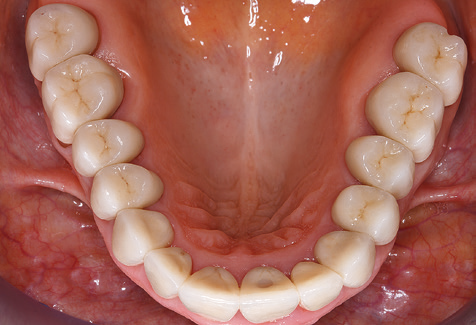

Eine 52­-jährige Patientin stellte sich nach Zahnverlust im 3. Quadranten erstmals 2004 vor. Sie hatte den Wunsch nach einer prothetischen Neuversorgung. Im Rahmen der parodontologischen und radiologischen Diagnostik zeigte sich ein ausgeprägter parodontologischer Behandlungsbedarf. Die Zähne 48, 28, 27 zeigten zudem eine infauste Prognose und wurden entfernt (Abb. 1). Nach der erfolgreich abgeschlossenen systematischen PAR­Therapie wurde eine festsitzende implantatprothetische Versorgung mit Insertion von fünf Implantaten in Regio 35, 36, 37 und 46, 47 durchgeführt. Die prothetische Versorgung der natürlichen Zähne erfolgte mit verblendeten Zirkonoxidkeramikkronen, die Implantate wurden mit zweiteiligen individuellen Zirkonoxidabutments und ebenfalls verblendeten Kronen aus einer Zirkonoxidkeramik versorgt (Cercon base colored, Dentsply Sirona Lab). Die definitive Insertion der prothetischen Versorgung erfolgte im Jahr 2005.

Die Patientin befindet sich weiterhin in einem halbjährlichen Intervall für die UIT. Nachfolgend werden am Beispiel dieser Patientin die einzelnen Arbeitsschritte einer strukturierten UPT­Sitzung aufgezeigt, so wie sie nahezu unverändert über den gesamten Funktionszeitraum von immerhin zwölf Jahren durchgeführt wurden. Natürlich wurden über diesen Zeitraum einige neue Materialien und Geräte in das Konzept integriert. In diesem klinischen Fallbericht wird das aktuelle Material­ und Gerätekonzept präsentiert.